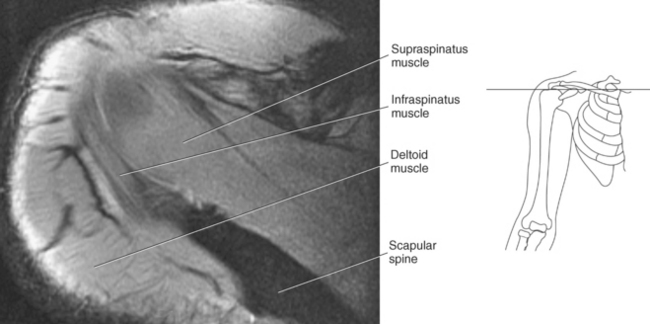

The scapula is a triangular-shaped flat bone that forms the posterior portion of the shoulder girdle. It has a medial margin, a lateral margin, and a superior margin. The margins are separated by the superior, inferior, and lateral angles (Figures 9.2 and 9.3). The anterior surface of the scapula, subscapular fossa, is flat and slightly concave. The posterior surface of the scapula is divided by the scapular spine into a smaller supraspinous fossa, and a larger infraspinous fossa (Figure 9.7). Four projections of the scapula provide attachment sites for the muscles and ligaments contributing to the shoulder girdle. These include the scapular spine, acromion, coracoid process, and glenoid process (Figures 9.7 through 9.10). The scapular spine arises from the upper third of the posterior surface of the scapula and extends obliquely and laterally to give rise to a flattened process termed the acromion. Located on the anterolateral surface of the scapula is a beaklike process termed the coracoid process, which arises just medial to the glenoid process and functions to protect the shoulder joint, which lies beneath it. The coracoid process is an attachment site for the pectoralis minor, short head of the biceps brachii, and the coracobrachialis muscles. The scapular notch is located just medial to the coracoid process, on the superior margin of the scapula and allows for the passage of the suprascapular nerve (Figure 9.2). The glenoid process, the largest of the projections, forms the lateral angle of the scapula and ends in a depression called the glenoid fossa (glenoid cavity) (Figures 9.7 through 9.9). There are two tubercles associated with the glenoid fossa, an upper supraglenoid tubercle and a lower infraglenoid tubercle, which serve as attachment sites for the biceps brachii and triceps brachii (Figure 9.8). The shallow articular surface of the glenoid fossa joins with the relatively large articular surface of the humeral head to create the freely moving glenohumeral joint (Figures 9.2, 9.3, 9.11, and 9.12).

Muscles of the scapula are described in Table 9.2 and demonstrated in Figures 9.34 through 9.52. The large deltoid muscle originates on the clavicle, acromion, and scapular spine to blanket the shoulder joint as it extends to insert on the deltoid tuberosity of the humerus. This powerful muscle forms the rounded contour of the shoulder and functions primarily to abduct the arm (Figure 9.48). The teres major muscle is a flat rectangular muscle that adducts and medially rotates the arm. It extends from the inferior angle of the scapula to the medial aspect or lip of the intertubercular groove of the humerus (Figure 9.49, A). The four remaining muscles, supraspinatus, infraspinatus, teres minor, and subscapularis, closely surround the scapula and compose the rotator cuff (Figures 9.49 through 9.52). The rotator cuff provides dynamic stability to the shoulder joint and allows for adduction, abduction, and rotation of the humerus. The supraspinatus, infraspinatus, and teres minor muscles are located on the posterior aspect of the scapula. The tendons of these muscles insert on the greater tubercle of the humerus. The supraspinatus muscle lies in the supraspinous fossa of the scapula and helps to abduct the arm. The tendon of the supraspinatus muscle is the most frequently injured tendon of the rotator cuff because of possible impingement as it extends under the acromioclavicular joint and continues over the humeral head (Figure 9.49, B). The infraspinatus muscle is a triangular muscle that lies below the scapular spine in the infraspinous fossa. It acts to laterally rotate the arm (Figure 9.49, A). Lying along the inferior border of the infraspinatus muscle is the elongated teres minor muscle, which also acts to laterally rotate the arm (Figure 9.49, B). The subscapularis muscle is the only muscle of the rotator cuff located on the anterior surface of the scapula; its tendon inserts on the lesser tubercle of the humerus (Figures 9.50 through 9.52). The subscapularis muscle acts to medially rotate the humerus. See sequential images through the shoulder (Figures 9.34 through 9.47).